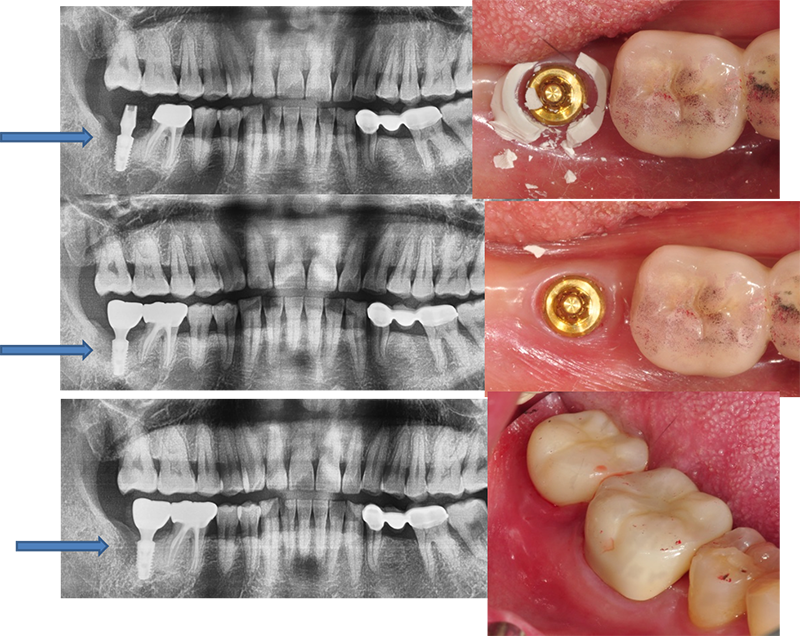

37¹ø 4.3 Á÷°æÀÇ ¿øÇöõÆ®

Á¦°ÅÇÏ´Ù°¡ ÈìÁýÀÌ ³¯ °Í °°¾Æ¼ Æ÷±âÇϰí

´ÙÀ½¿¡ ¾à¼Ó Àâ¾Ò´Âµ¥ ȯÀÚµµ Àúµµ ¹Ì·ç´Ù°¡ ÀÌ Áö°æµÊ.

ÆÄ³ë¶ó¸¶ »ó

°á±¹ ÇȽºÃÄ Á¦°Å

¾Æ¸¶µµ ±³ÇÕ¿¡ ¹®Á¦°¡ ÀÖ¾ú´ø µí

37¹ø abutment ÆÄÀý, µÚÂÊ¿¡ 8¹øÀÌ º¸À̰í, fixture Á÷°æÀÌ 5.0, Á¶±Ý ÈìÁýÀÌ ³ªµµ µÈ´Ù´Â »ý°¢À¸·Î Á¦°Å¼ö¼úÀ»

Çß´Ù.

3¹ø¿¡

³ª´²¼ °Ü¿ì Á¦°ÅÇÑ °æ¿ì